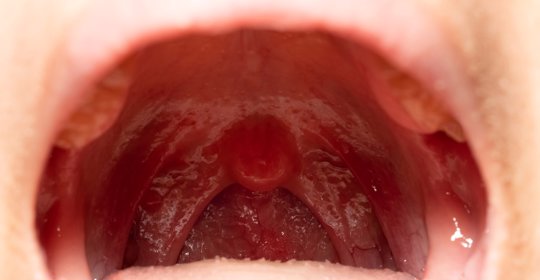

淋巴結腫痛的原因是什麼?

淋巴結腫痛可能由EB病毒感染、巨球蛋白血癥、非何杰金氏淋巴瘤(NHL)、胃癌、結核病等疾病引起,需要根據具體病因進行針對性治療。建議患者及時就醫以確定診斷並接受適當治療。

淋巴結腫大原因

淋巴結腫大的原因可能有EB病毒感染、巨球蛋白血癥、非何杰金氏淋巴瘤(NHL)、胃癌、結核病等,需要根據具體病因進行針對性治療。建議患者及時就醫以確定診斷並接受適當治療。